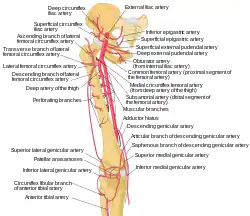

The femoral vein and its tributaries. Schema of the arteries arising from the external iliac and femoral arteries.

Schema of the arteries arising from the external iliac and femoral arteries. Anterior abdominal wall.Intermediate dissection.Anterior view

Anterior abdominal wall.Intermediate dissection.Anterior view